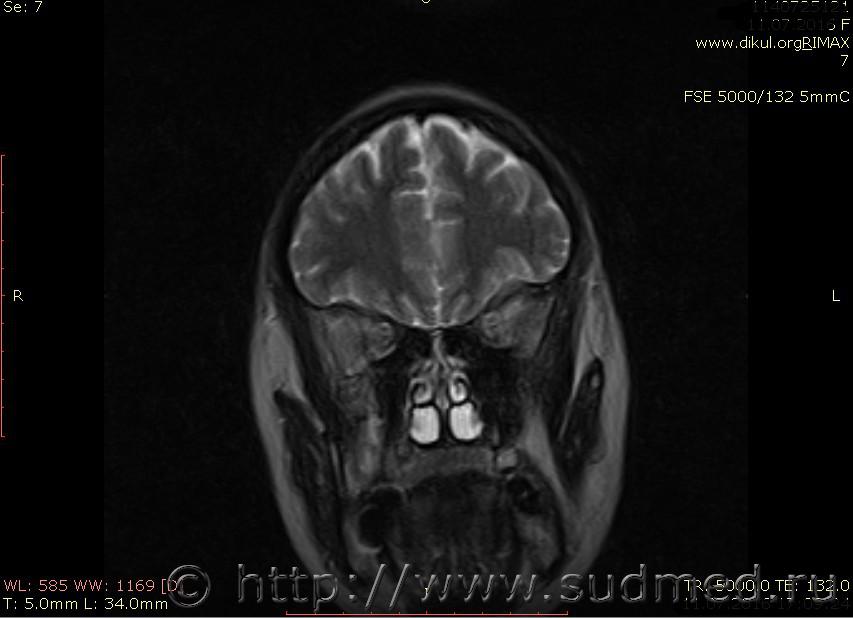

МРТ головного мозга показало: МР-данных за наличие очаговых изменений в веществе головного мозга на момент исследования не выявлено. МР-признаки нарушения соотношения в атланто-осевом суставе. Определяется ассиметрия положения зубовидного отростка С2 относительно боковых масс С1(справа 6,5; слева 4 мм.)

Сама по себе эта информация даёт основания подозревать вывих первого шейного позвонка, но однозначно не свидетельствует о наличии вывиха. Нужно смотреть на снимках наличие реакции со стороны мягких тканей, в т.ч. связочного аппарата, нужно анализировать особенности неврологической патологии, её динамику и проч.

Запрошен электронный вариант снимков из учреждения, где делалось МРТ. Т.к. с самого снимка делать копии не получается,очень мелкие кадры. Завтра попробую вставить в сообщение. (Но СМЭ снимок не смотрел, смотрел только мед.карту, в которой находилось описание МРТ).

Посмотрите пожалуйста снимки, надеюсь на них видны позвонки С1,С2?

Прошу прощения, попробую снова прикрепить файлы. Данные учреждения и пациента убраны.